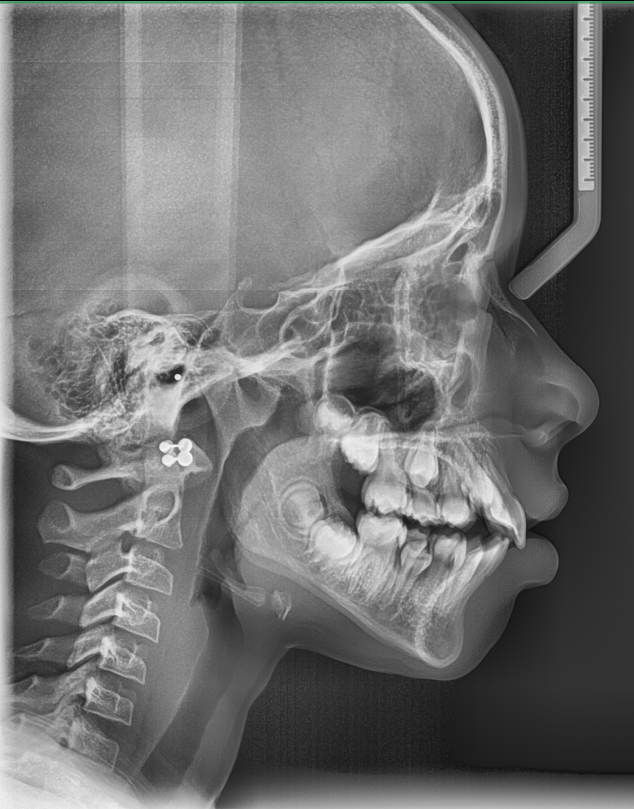

Case Study – Chloe.W – Early Intervention Orthodontics – Severe Overjet

Adaptive Orthodontics Pre-Op Analysis – 2020-11-25 Age : 9 Class 2 div I and div IIMixed DentitionLower lip entrapment NORMALLY LOWER LIP ENTRAPPED BEHIND UPPER ANTERIOR NORMALLY LOWER LIP ENTRAPPED BEHIND UPPER ANTERIOR PROCLINE (OVERJET) UPPER ANTERIORDIASTEMA (SPACING) – TONGUE THRUSTLOWER LIP ENTRAPMENTNARROW (GOTHIC) ARCHDEEP BITE – SOFT TISSUE TRAUMA STAGE 1 RETRACT UPPER ANTERIORS… Read.